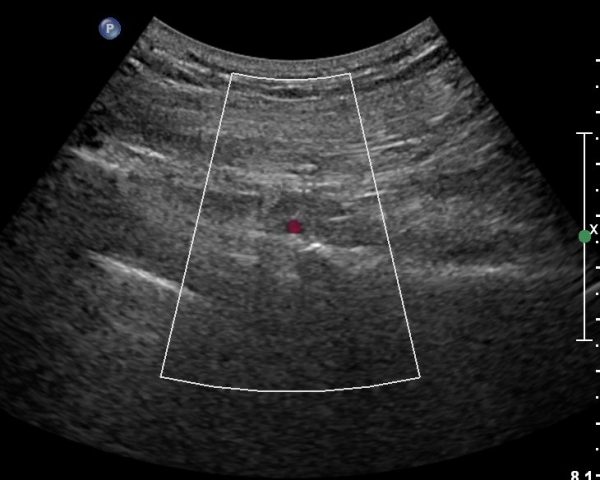

ŽÃÍÀÚ¸¦ ´Ù¸®ÂÊÀ¸·Î ¼öÆò À̵¿ÇÏ¸é ½ÉÃþ¿¡¼­ Àå°ñÀÌ »ç¶óÁö°í »õ·Î¿î ±ÙÀ°ÃþÀÌ º¸À̴µ¥ À̰ÍÀÌ ÀÌ»ó±ÙÀ̰í ÀÌ»ç±Ù ½ÉÃþ¿¡¼­ Á°ñ½Å°æ¸£ °üÂûÇÒ ¼ö ÀÖ´Ù(»çÁø 2, 3).